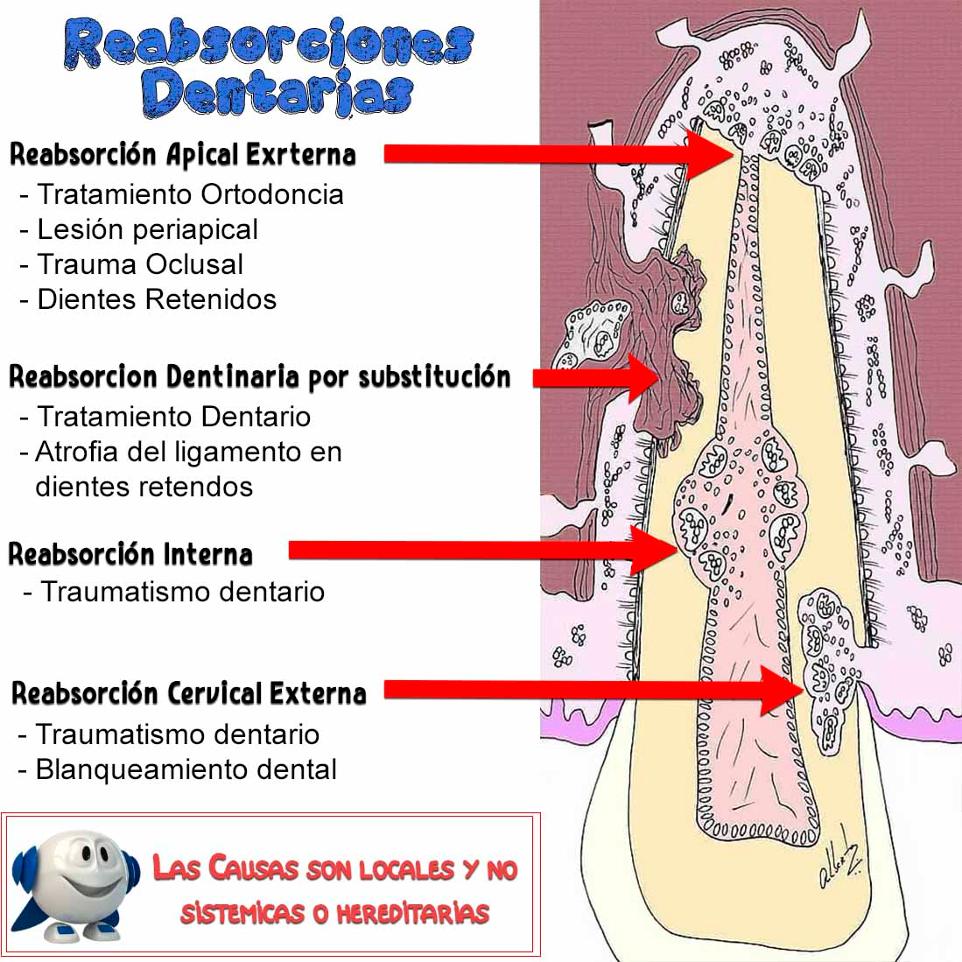

La presentación de casos radiográficos, permite la visualización de patologías que son muy difíciles de ver en la clínica, ya que muchos de ellos son hallazgos radiográficos. Además permite ver y refrescar clasificaciones y conceptos muchas veces estudiados. La presentación de los mismos no incluyen datos personales, mas que edad y sexo, que suelen ser importantes para ver la correlación entre la patología, su aparición o forma de presentación.

Esto también refleja las patologías que aquejan a los pacientes de nuestra región, y trata de ser un faro tanto para profesionales como alumnos que estudian dichas lesiones.